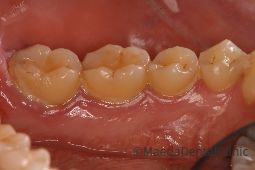

歯肉炎

歯垢(プラーク)が付着して放置しておくと、歯肉が炎症を起こします。この歯肉の炎症を歯肉炎と呼び、歯肉の炎症が進行すると、歯槽骨にまで炎症が波及してしまいます、これを歯周炎と呼びます。歯肉炎は症状が強くないため、そのまま放置してしまいがちです。歯周炎に進行しないように早期に治療しましょう。